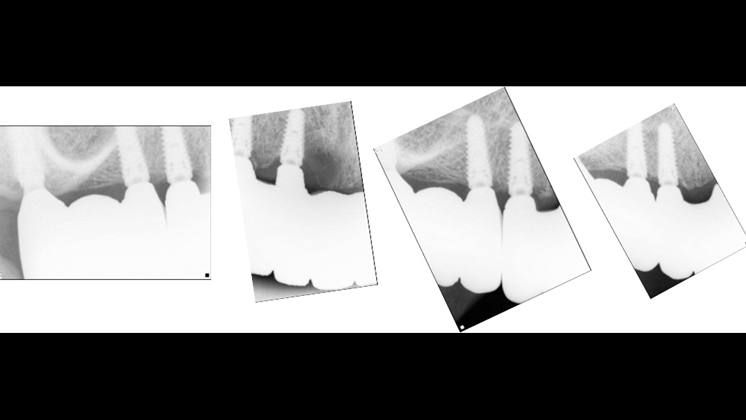

Clinical case: Full-mouth implants for mandibular & maxilla - restored using mixed prostheses

- Courtesy of Dr. Hyun Jun Kim, Korea -

Keywords

AnyRidge, full-mouth implants, mandibular, maxilla, edentulous, full mouth rehabilitation, Octa abutment, long-term clinical case, biological stability, Dr. Hyung Jun Kim

Products:

AnyRidge implant system